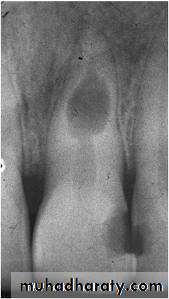

- Insufficient periodontal support:

Periodontal or periapical disease → alveolar bone loss →lack of periodontal support.

Inadequate crown - root ratio.

Caries of root and caries of bifurcation

Internal resorption with perforation.

Vertical root fracture.